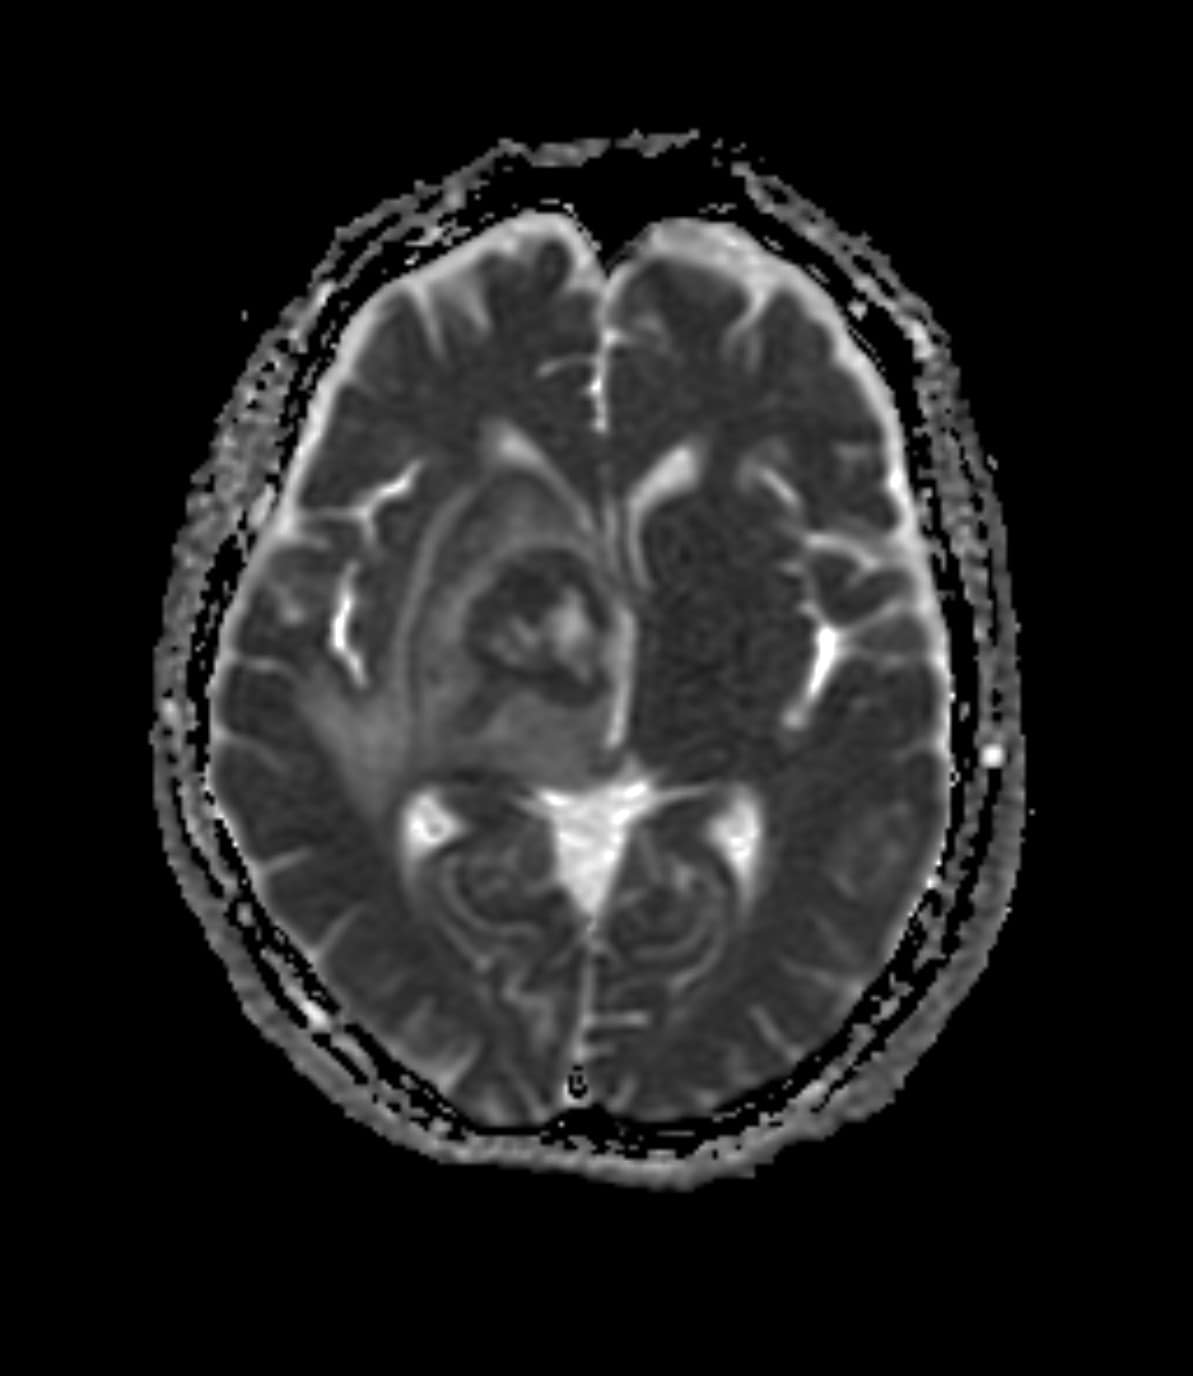

右基底核~視床~右中脳腹側にかけて均一で強いリング状増強効果を呈する腫瘤を認める。周囲に浮腫と思われるFLAIR 高信号域を認める。主病変の濃染部分はFLAIR等信号、DWI 高信号、ADCmap 低信号を呈している。MRS(TE=144)でChoが上昇、CrとNAAが低下している。ASLでは血流の顕著な上昇は認めない。中枢神経原発悪性リンパ腫(PCNSL)が疑われた。脳腫瘍生検の結果、中枢神経原発悪性リンパ腫(PCNSL)と診断された。